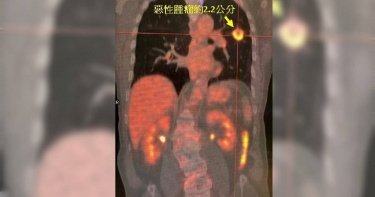

一名82歲老翁,吸菸長達60年,並未出現咳嗽氣喘等症狀,在他院照過X光發現疑似有腫瘤,求診中國醫藥大學新竹附設醫院胸腔內科主任莊子儀,莊子儀透過醫學影像科病理切片,診斷老翁罹患早期肺癌。經過胸腔外科主任陳品儒和胸腔外科醫師林佳穎執行微創手術,切除約2.2公分的惡性腫瘤,手術順利,目前老翁持續三個月回門診追蹤。莊子儀主任表示,因為老翁年事已高,安排肺部檢查確認肺功能,同時也經過正子攝影,確認癌細胞沒轉移才能手術。陳品儒主任表示,以病患腫瘤大小,應該要切除整片左上肺葉,但考量患者高齡,術後剩餘肺功能在維持日常生活會比較辛苦,因此與家屬討論後,決定執行微創手術,在安全範圍內將腫瘤切除,保留肺部功能,維持日常生活。胸腔外科醫師林佳穎指出,因為老翁吸菸長達60年,導致肺部有明顯的肺氣腫變化,所有的針孔都很容易漏氣,因此醫護團隊使用組織膠以及帶墊片的特殊縫合釘順利切除腫瘤。目前病患回診追蹤,術後電腦斷層,證實病灶已完整切除未有轉移,接下來將以三個月為間隔追蹤。莊子儀主任表示,早期的肺癌可能不到兩公分,體積所佔肺部的比例很小,因此,不太可能有症狀,肺癌有症狀來就醫可能就比較晚期,有症狀是因為腫瘤已經塞住氣管才會咳嗽,或是腫瘤侵犯到肋膜腔產生積水,病人除了咳嗽也會喘,如果肺癌轉移到骨頭或腦部等器官,會出現疼痛的症狀或頭暈頭痛。莊子儀提醒,國健署針對高風險的族群,提供低劑量的胸腔電腦斷層檢查。首先,年紀越大風險越高,基因突變機率高,40歲以上女性、50歲以上男性。其次,有家族病史像是父母、兄弟姊妹、兒女罹肺癌。另外,一天抽一包菸,超過三十年以上。以及空汙問題越來越嚴重,煮飯的油煙也是高風險,沒有抽菸的婦女也可能得到肺癌,以及特定職業,像是交通警察、餐飲業者、高科技業者容易吸到重金屬的粉塵也是高風險。診斷第四期的病人超過50%,只有五年存活率為10%-20%,但是若為第0期或者第1期的病人,五年的存活率為9成,因此,早期發現早期治療。